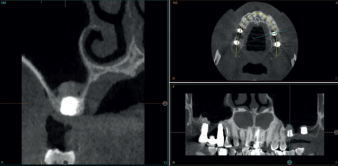

Todos los pacientes fueron tratados por un mismo cirujano, para la realización de la inserción de los implantes y la técnica de elevación transcrestal. Antes de la inserción de los implantes se utilizó una premedicación antibiótica consistente en amoxicilina 2gr vía oral una hora antes de la intervención y paracetamol 1 gramo vía oral (como analgésico). Posteriormente los pacientes prosiguieron con un tratamiento de amoxicilina 500-750 mg vía oral cada 8 horas (según peso) durante 5 días. Todos los pacientes fueron estudiados antes de la inserción de los implantes mediante modelos diagnósticos, exploración intraoral y realización de una tomografía computerizada de haz cónico (CBCT), analizado posteriormente mediante un software específico (BTI-Scan III). La cirugía se lleva a cabo mediante la técnica de fresado biológico descrita por nuestro grupo de estudio previamente, a bajas revoluciones, sin irrigación10, hasta ser finalmente completada mediante la elevación transcrestal con las fresas de corte frontal que se emplean también a bajas revoluciones. Una vez la membrana es accesible mediante la perforación crestal se despega mediante una ligera presión y se inserta el implante con el motor quirúrgico fijado a 25 Ncm y 25 rpm finalizando la inserción del implante con la llave dinamométrica. Todo el hueso recogido con las fresas se conserva en PRGF-Endoret fracción 2 sin activar, para posteriormente ser utilizado como injerto óseo particulado en la elevación, sin otros materiales accesorios9,12. Una vez finalizada la cirugía se realiza una radiografía periapical con paralelizador que será la que se utilice como punto de partida. Los pacientes acuden posteriormente para la realización de radiografías periapicales de control, tomadas con la misma técnica y sobre estas radiografías se realizan las mediciones necesarias para comprobar la estabilidad y pérdida ósea crestal de los implantes. La medición de la pérdida ósea marginal se realizó en la última radiografía periapical realizada con posicionador de seguimiento.

En la Figura 2 se muestran los diámetros y longitudes de los implantes incluidos en el estudio en función de los milímetros de cresta ósea residual en altura. La densitometría media de la zona de inserción del implante del grupo fue de 293,33 HU (+/- 144,99). El torque medio de los implantes estudiados fue de 27,33 Ncm (+/- 16,99). Todos los implantes se cargaron en dos fases quirúrgicas y en todos se llevó a cabo una elevación de seno transcrestal con injerto óseo autólogo particulado obtenido del fresado, embebido en PRGF-Endoret como marterial de injerto. En ninguno de los casos se registraron complicaciones relativas a la cirugía. Los implantes presentaron un seguimiento medio de 13,33 meses tras la carga (+/- 3,09), no encontrándose complicaciones ni fracasos durante este tiempo de seguimiento, por lo que la supervivencia fue del 100%. Todos los implantes fueron rehabilitados mediante prótesis múltiple atornillada mediante elemento intermedio (transepitelial múltiple, Multi-im®), encontrándose dos de los implantes ferulizados a otros de la misma longitud (4,5 mm) y el resto a longitudes mayores. La ratio corona-implante medio para el grupo de estudio fue de 2,43 mm (+/-0,45). La pérdida ósea mesial final media de todos los implantes fue de 0,42 mm (+/- 0,51) y la pérdida ósea distal final media de 0,16 mm (+/-0,34). En las Figuras 3 –13 se muestra uno de los casos incluidos en el estudio.